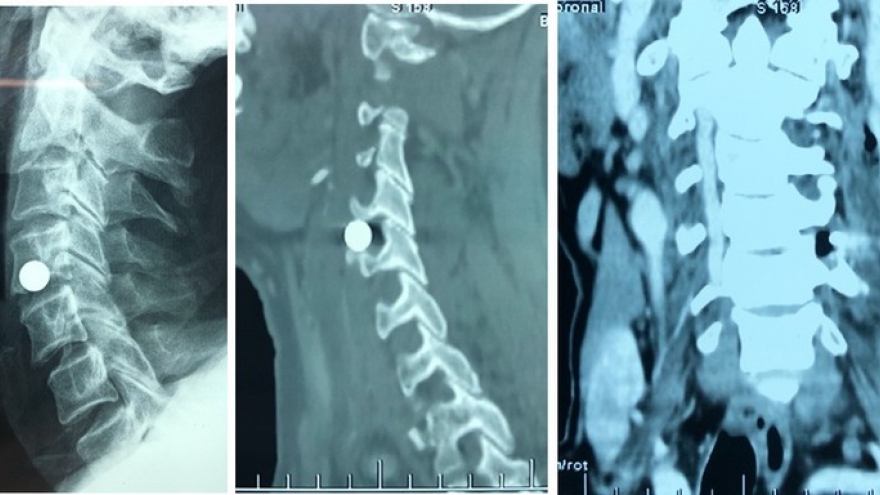

VOV.VN - Bệnh viện Chợ Rẫy vừa điều trị, giải độc thành công cho một trường hợp bị nhiễm độc kim loại nặng từ thuốc nam. Bệnh nhân này đã mất hàng trăm triệu đồng vì 2 năm dùng thuốc nam điều trị bệnh theo “truyền miệng”.